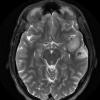

1A5 BCOR-BCORL1 Fusion (Case 1) T2 NoC - Copy